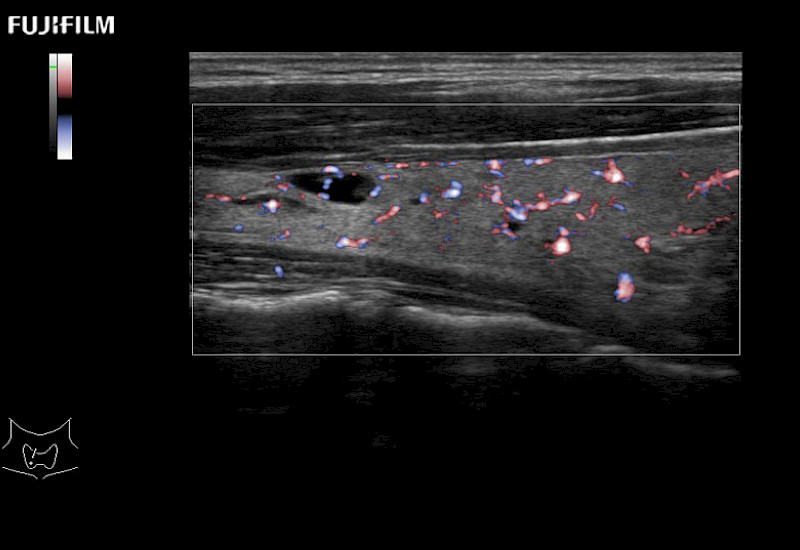

Exclusive linear array robotic surgery transducer.

Features:

Learn moreFujifilm Healthcare continues to listen to the experts, our neurosurgeons, by developing an ultrasound system specifically designed for the Operating Room.

Guidance is the fundamental purpose for all of our surgical ultrasound technology. Fujifilm Healthcare is committed to designing tools that help neurosurgeons navigate inside the human body and provide the necessary information to immediately make critical surgical decisions.

With the ARIETTA Precision the next level of surgical ultrasound is here.